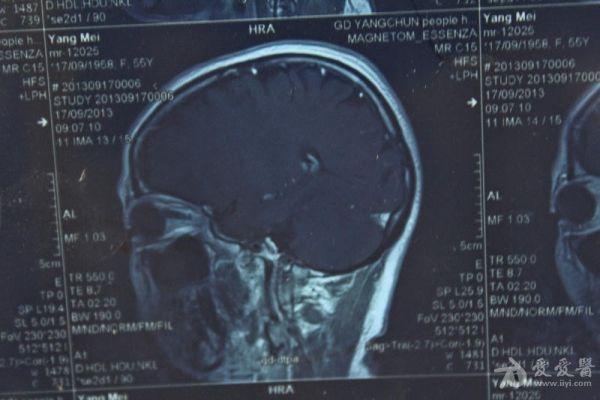

脑部占位病变CT,MRI图片,请帮忙诊断

最近感图样,无其它脑病病史

考虑脑膜瘤!!

磁共振没有平扫,增强矢状位没找到病灶。像脑膜瘤。

图片不是很清楚,应该是脑膜瘤!